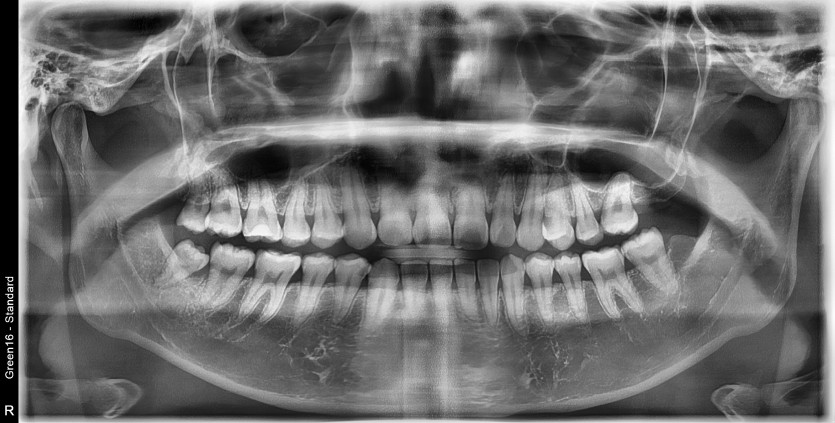

#18,48 사랑니 발치

구강외과 전문의가 당일발치 했습니다.